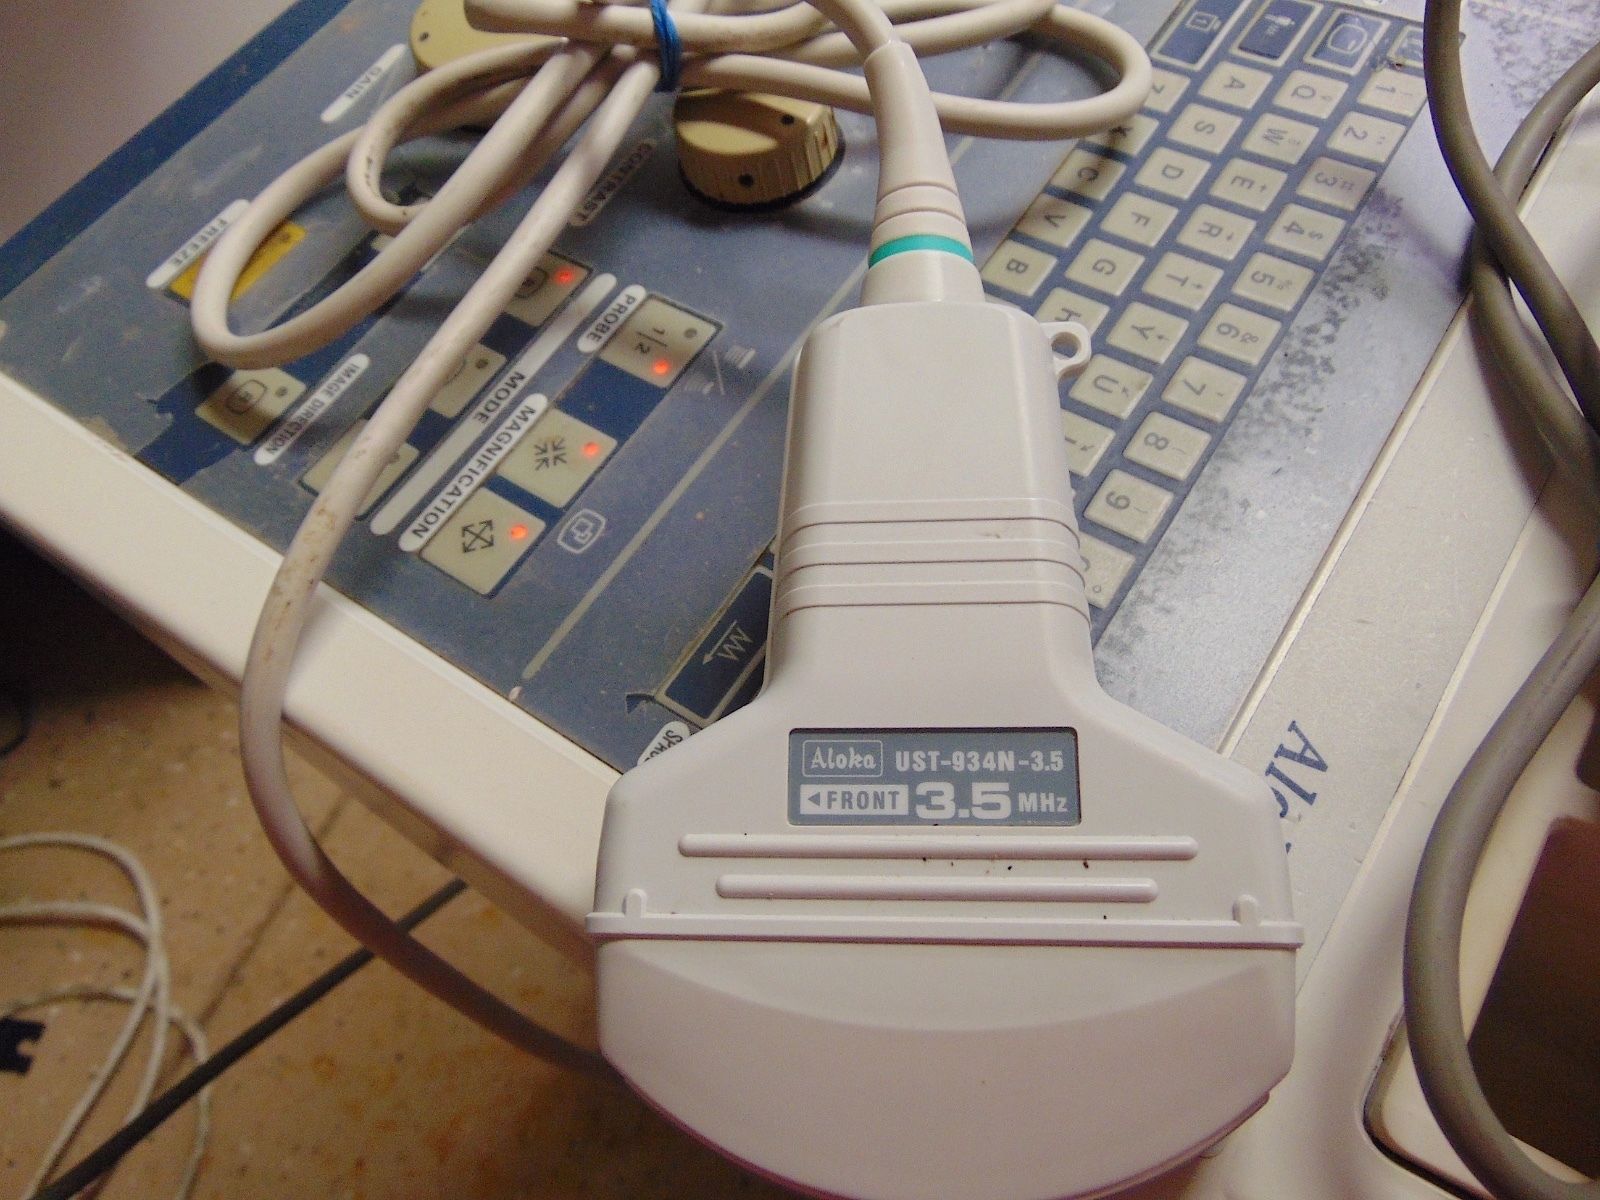

Seller Notes:âThe unit powers on and the monitor works good. Comes with a remote control unit and a functioning ultrasound probe. Unit is in good cosmetic condition but does show wear from being used.â

Brand: Aloka

Model: SSD-620